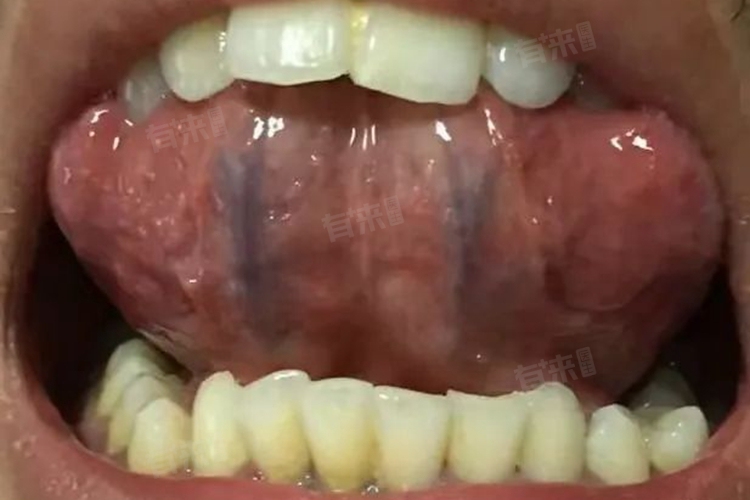

女人舌底青筋黑可能是正常生理现象,也可能是病理状态的表现,在出现此情况时,建议结合自身症状进行判断,如有疑虑或伴有其他不适症状,应及时就医检查并治疗。

- 颜色差异:正常情况下,舌底的青筋即舌静脉,可能呈现紫色或紫黑色,这是由于静脉血中含氧量较低所致。因此,女性舌底青筋黑可能是正常的生理表现,无需过度担心。

- 静脉淤血:当血液循环出现障碍时,可能会引起静脉淤血,导致舌底青筋颜色加深甚至变为黑色,这种情况可能伴随局部水肿等症状,需要及时就医检查并治疗。